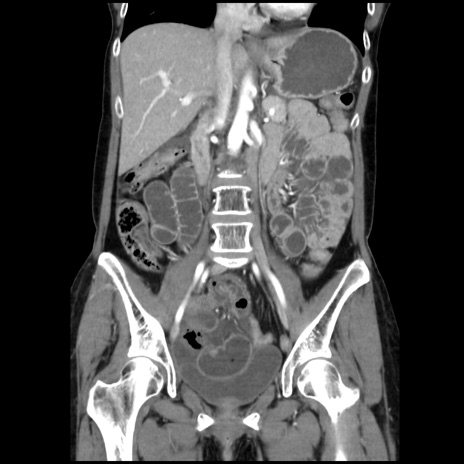

症例32(冠状断像)

【症例】40歳代 女性

【主訴】上腹部痛、嘔気・嘔吐

【現病歴】約9時間前頃から急に上腹部痛、嘔気、嘔吐が出現。改善しないため救急要請。

【既往歴】子宮頚癌(広汎子宮全摘術、放射線療法)、腸閉塞

【身体所見】腹部:平坦、軟、腸雑音亢進、上腹部を中心に腹部全体に圧痛あり。

【データ】WBC 8400、CRP 0.03